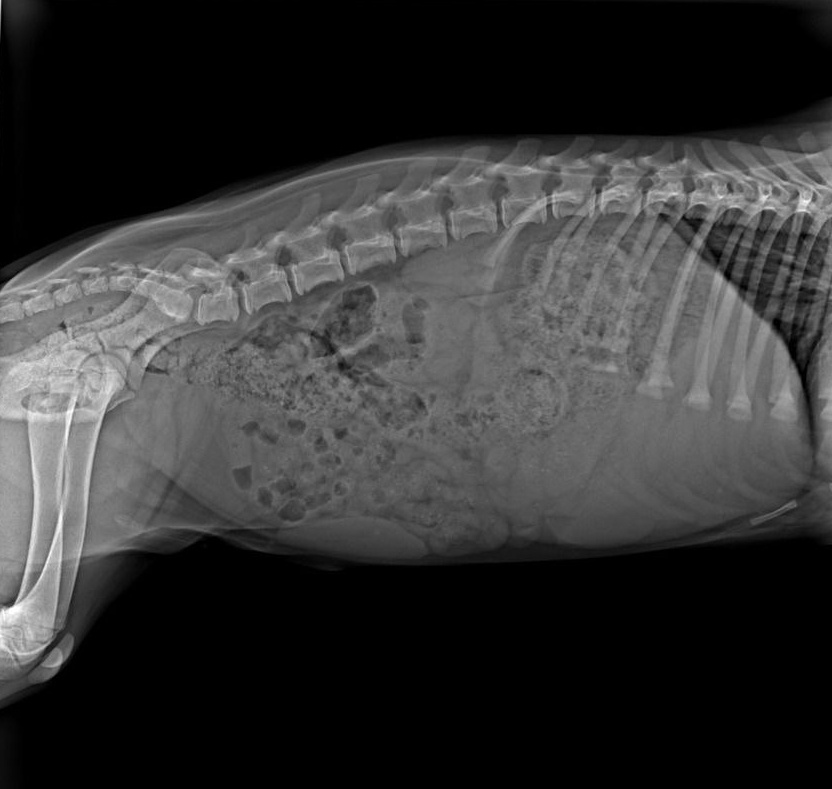

К нашему огромному облегчению и счастью, Цой оказался настоящим счастливчиком! Он чудом избежал серьезных травм, отделавшись ссадинами, гемaтомами и, конечно, сильным испугом. Мы сразу же сделали рентген задней лапки, на которую он хромал, и выдохнули — переломов нет, только сильный ушиб!